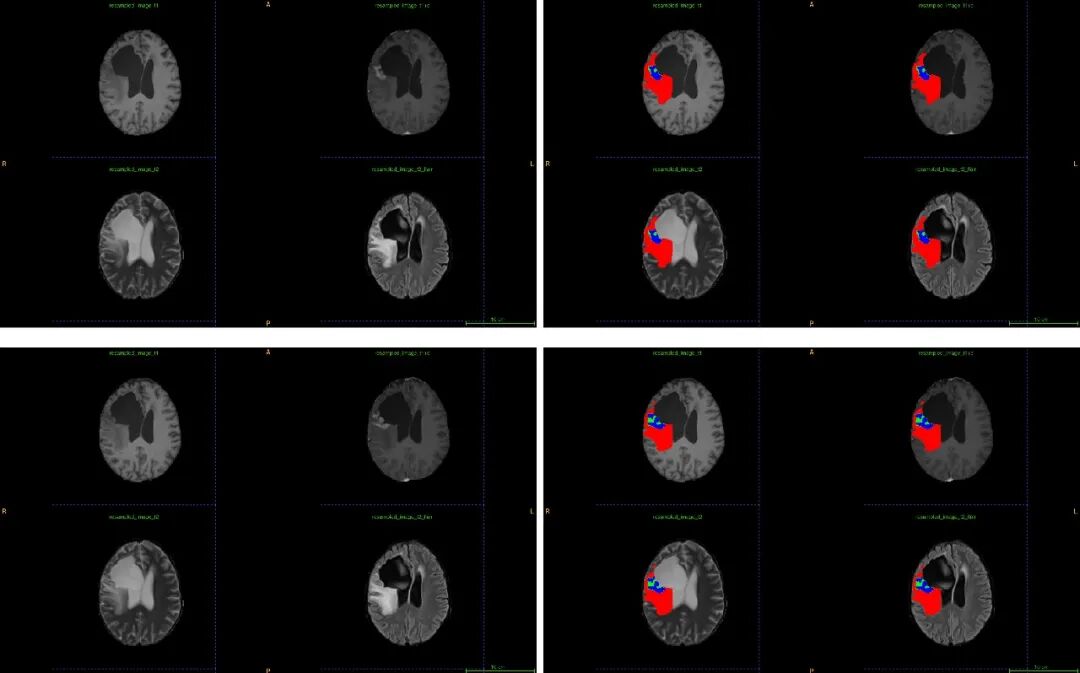

值得一提的是,IEES2.0系统的医学影像AI智能辅助分割/勾画功能在脑胶质瘤的识别和勾画方面取得了重大突破,这一直以来都是医学影像领域的一大挑战。脑胶质瘤是一种源自神经胶质细胞的恶性肿瘤,由于其位置深处、边界模糊、与周围组织的交织以及侵袭性生长等特点,常常导致阅片专家在诊断时困难重重。然而,借助IEES2.0系统的AI智能辅助分割/勾画功能,使研究者能够清晰地界定脑胶质瘤的边界,并精确勾画出肿瘤的范围,从而为诊断提供了有力支持。

红色代表水肿, 绿色代表液化坏死, 蓝色代表强化部分